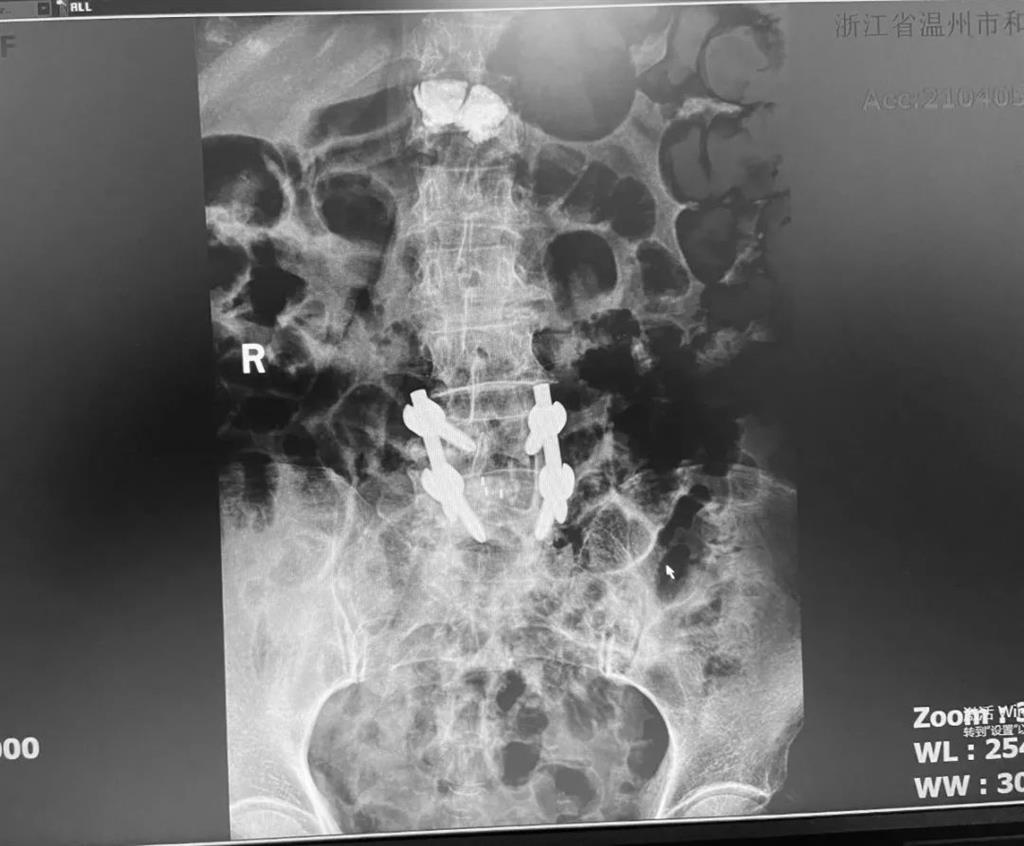

據(jù)了解,脊柱內(nèi)鏡下腰椎融合術(shù)只需要打幾個(gè)“鑰匙孔”即可完成。聽起來是不是很簡單?在脊柱內(nèi)鏡下,劉丹主任先后為患者進(jìn)行了椎管減壓、椎間盤摘除,再實(shí)施椎弓根螺釘放置、椎體植骨融合內(nèi)固定,一系列步驟有條不紊。

術(shù)中只需切開4個(gè)如“鑰匙孔”般大小的孔道